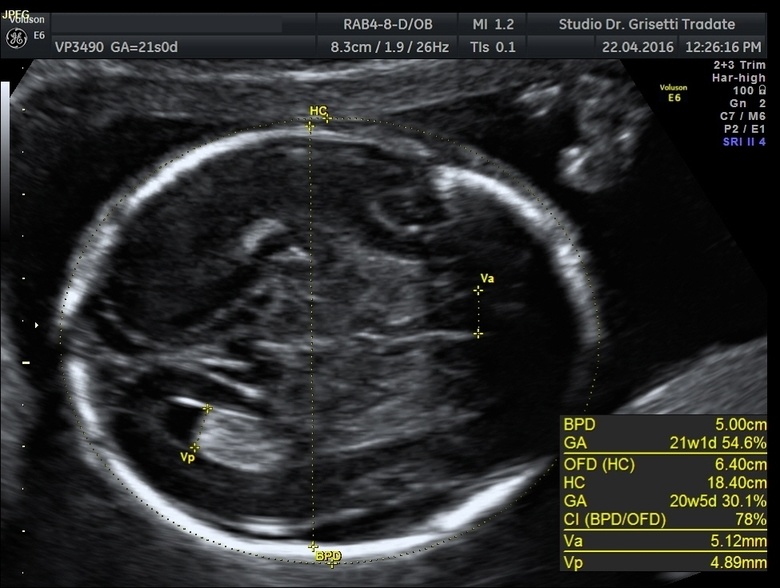

Ecografia Ostetrica Morfologica

Dalla 20-22 settimana di gravidanza. Meglio definibile come "ecografia d'organo", in quanto vengono prese analiticamente in esame le seguenti strutture fetali: cranio, cervello, cervelletto (3D), massiccio facciale, collo, torace, cuore, addome, stomaco, reni, vescica, arti, mani, piedi, dita, placenta, cordone ombelicale, liquido amniotico, flussi ombellicali e materni.

Comprende lo studio della forma, profilo, le misurazioni biometriche e la valutazione delle strutture endocraniche: emisferi celebrali, falce, ventricoli laterali, trigono, cervelletto, cisterna posteriore, verme cerebellare, quarto ventricolo, corpo calloso, cavo del setto pellucido, orbite, cristallini, massiccio facciale, palateo osseo, ossa nasali, lingua, mandibila, inserzione padoglioni auricolari, ecc.